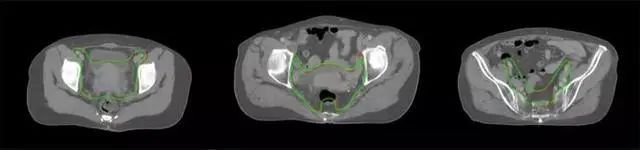

放射治療,簡稱放療,是治療腫瘤主要手段之一,利用放射線破壞照射區(qū)(靶區(qū))的細胞,使腫瘤細胞停止分裂直至死亡,醫(yī)生通常把放射治療形象的比喻為“打靶”,放療前精準勾畫腫瘤靶區(qū)范圍是腫瘤放射治療的關鍵步驟。傳統(tǒng)的靶區(qū)勾畫醫(yī)生會根據(jù)患者多張CT、MRI影像片憑借經(jīng)驗進行,比較耗時,治療的病人數(shù)量也有限,且靶區(qū)勾畫缺少行業(yè)統(tǒng)一的規(guī)范和標準,無法達到同質化,勾畫精確度不理想。

技術原理

基于深度學習人工智能的放療靶區(qū)智能勾畫技術和自動計劃技術,基于全面的市場調研和臨床專業(yè)意見,采用獨創(chuàng)的基于小樣本量的人工智能算法,實現(xiàn)放療靶區(qū)和危及器官的快速全自動勾畫。

產(chǎn)品優(yōu)勢

縮短至幾分鐘內便可完成,大幅提升了放療效率,且人工智能平臺完成的靶區(qū)勾畫可基本滿足臨床醫(yī)生需求,專家只需審核時細微調整,可顯著提高靶區(qū)勾畫的規(guī)范化及精準度,讓放療智能化,標準化??筛采w食管癌、鼻咽癌、直腸癌、宮頸癌、肺癌等多種病種。